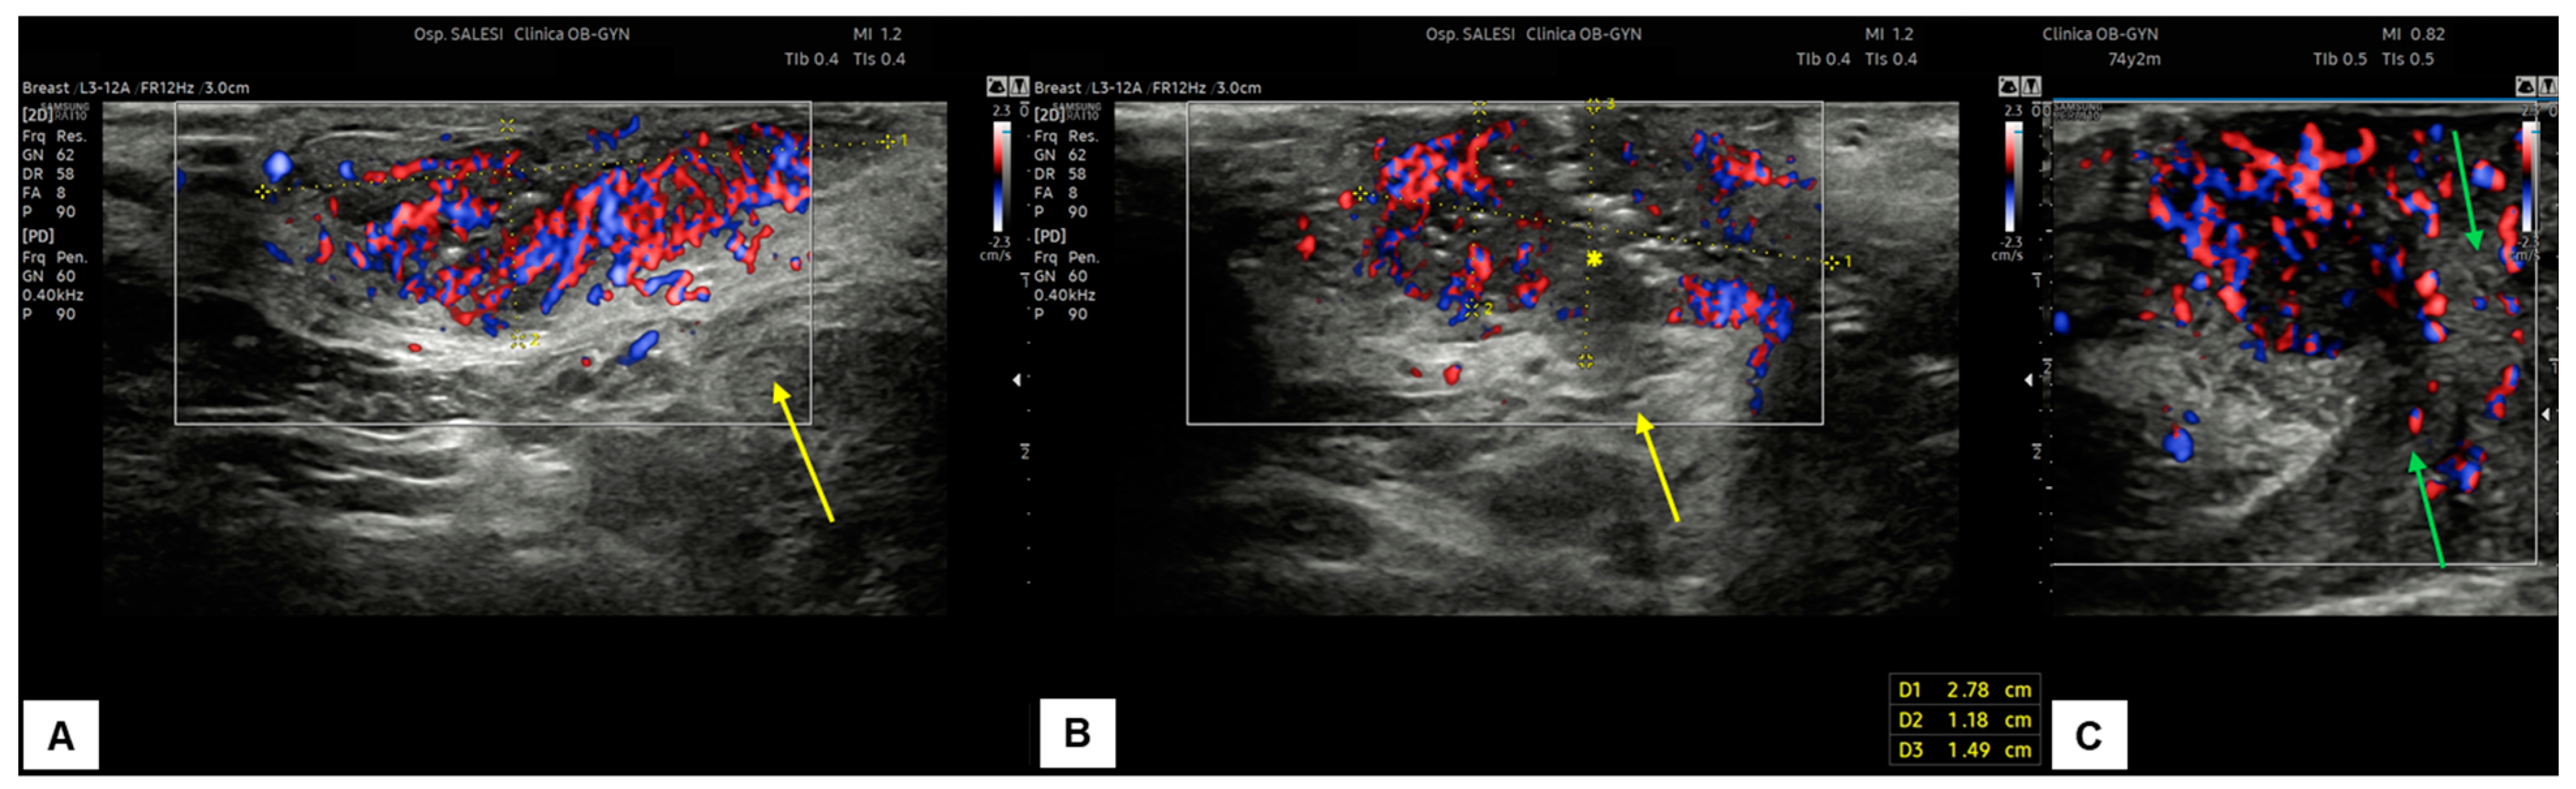

7.3. Malignant Vulvar Lesions

- Measurement from the adjacent most superficial dermal papilla to the deepest point of invasion

- Measurement from the basement membrane of the deepest adjacent dysplastic (tumor-free) rete ridge to the deepest point of invasion, which should be the technique of choice. Because epidermal ridges cannot be distinguished on ultrasonography, our suggestion is to take the lower hyperechogenic line of the epidermal layer as a reference (Figure 10).